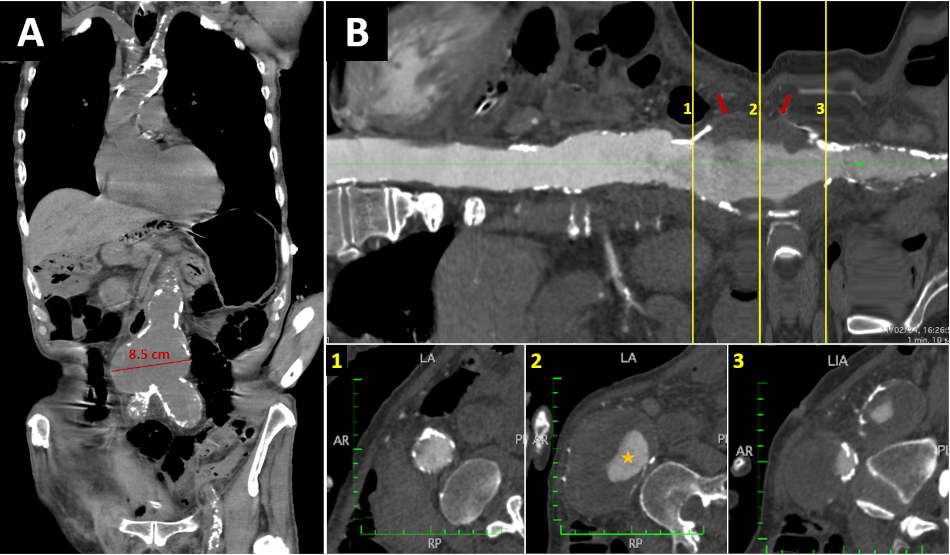

Figure 5

A. Non-contrast thoracoabdominal CT - Coronal section. Severe calcification of the aorta is observed, predominantly in the aortic arch and abdominal aorta. Also, there is an aneurysmal dilatation of the infrarenal aorta with a maximum diameter of up to 8.5 cm. B. Longitudinal reconstruction of the aorta. The transverse sections at the level of the abdominal aortic aneurysm demonstrate the calcification of the abdominal aneurysm wall along with the presence of extensive mural thrombus (red arrows) and a reduced luminal diameter (orange star).

AR: anterior and right; CT: computed tomography; LA: left and anterior; PI: posterior and inferior; RP: right and posterior.